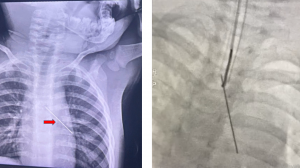

Vừa qua, bệnh viện Nhi đồng Thành phố tiếp nhận trẻ L. N. H. 12 tuổi, nam, ngụ ở Vĩnh Lộc A, Bình Chánh, nhập viện vì thở mệt. Bệnh sử 2 ngày, N1: em sốt không rõ nhiệt độ, không ói, không ho, tiêu tiểu bình thường, khám bác sĩ tư không rõ điều trị. N2: em còn sốt, kèm ói 2-3 lần sau ăn, than mệt nhiều nên nhập bệnh viện Nhi đồng Thành phố trong tình trạng, lừ đừ, chi mát, mặt quay bắt nhẹ, thời gian phục hồi máu da kéo dài, da nổi bông tím, huyết áp tụt 70/50mmHg, nhịp tim 180 lần/ph, tiếng tim mờ, phổi phế âm đều, bụng mềm, xét nghiệm test nhanh SARS-CoV-2 dương tính, Real Time RT PCR dương tính CT 14, siêu âm tim ghi nhận tràn dịch màng tim lớp dịch dày 15-20mm, chức năng co bóp cơ tim kém EF dao động 30-35%, men tim tăng cao (CK-MB, troponin I tăng cao). Trẻ được chẩn đoán sốc tim – tràn dịch màng ngoài tim – viêm cơ tim – COVID-19 cấp tính. Trẻ được xử trí đặt nội khí quản thở máy, an thần, vận mạch adrenalin, dubutamin, noradrenalin, kháng virus, kháng viêm, kháng sinh, đặt dẫn lưu màng ngoài tim, tình trạng diễn tiến nặng, sốc không cải thiện, sức co bóp cơ tim tiếp tục giảm EF còn 25-30% nên được tiến hành thực hiện kỹ thuật oxy hóa máu qua màng ngoài cơ thể phương thức VA ECMO, điều chỉnh rối loạn điện giải, toan kiềm. Kết quả sau 6 ngày chạy ECMO tình trạng trẻ cải thiện dần, giảm và ngưng được thuốc vận mạch, cai được ECMO, máy thở, thở khí trời, tỉnh táo, được chuyển khoa tim mạch tiếp tục điều trị. Đây là trường hợp trẻ mắc COVID-19 cấp tính nặng biến chứng viêm cơ tim màng ngoài tim.

Cấp cứu một trẻ hóc dị vật đường thở là cây kim cúc dài 3cm